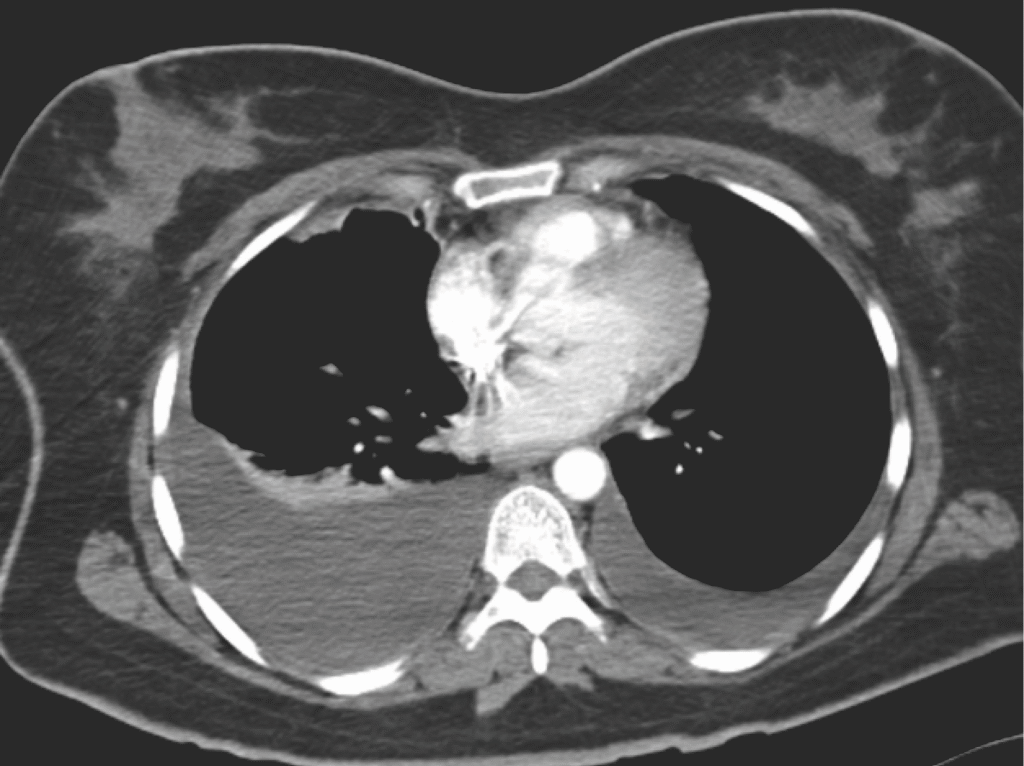

- CT Thorax: DD Tumor, Empyem